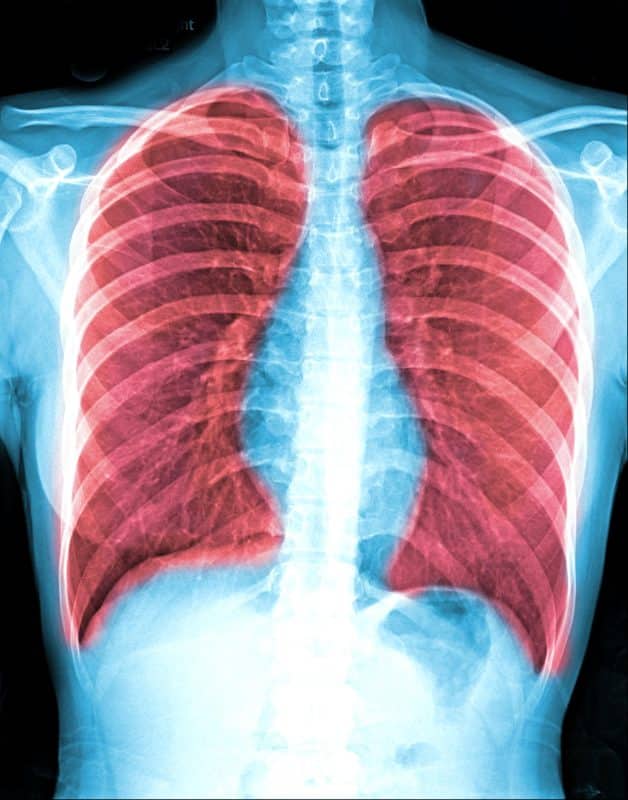

1. בדיקות הדמיה

- צילום רנטגן של החזה – מאפשר זיהוי מוקדי גידול ראשוניים בריאות.